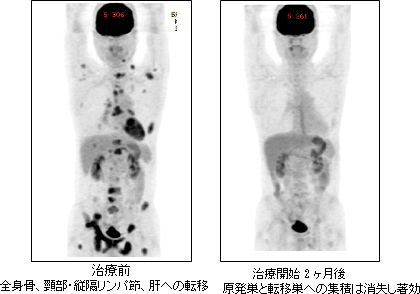

非小細胞肺がんの抗がん剤治療には、殺細胞性抗がん剤を用いた化学療法と、がん細胞の生存・増殖に関わる物質を選択的に抑える分子標的薬を用いた分子標的治療があります。化学療法を初回治療として開始する場合、プラチナ製剤(シスプラチン、カルボプラチン)と第3世代抗がん剤(ペメトレキセド、パクリタキセル、ドセタキセル、ゲムシタビン、ビノレルビン、塩酸イリノテカン、S1など)の2剤併用療法、さらに非扁平上皮癌の場合は、腫瘍の血管新生を促すVEGF(血管内皮増殖因子)の働きを阻害する分子標的薬であるベバシズマブを併用した3剤併用療法を行います。以前は、肺がんの化学療法は入院で多く行われていましたが、現在では副作用の管理の進歩もあり、外来で安全に続けることが可能となり、当院ではシスプラチンを含む併用療法なども外来で行っています。一方、分子標的薬である、EGFR(上皮成長因子受容体)を標的とした内服薬(ゲフィチニブ、エルロチニブ)やALK(未分化リンパ腫キナーゼ)融合蛋白を標的とした内服薬(クリゾチニブ)は、それぞれの標的に依存して増殖するがん細胞に特異的に作用することで、腫瘍の著明な縮小と進行抑制をもたらします(下図)。これらの薬剤により、一人ひとりのがんの特徴に合わせた「個別化治療」が可能となってきました。当院では、気管支鏡検査やCT下肺生検などによる肺がんの診断時に、得られたがん組織(細胞)に対してこれらの遺伝子について速やかに検索を行い、個々の患者さんに合わせた抗がん剤治療を選択しています。

全身転移をきたした肺がんに対するクリゾチニブ投与例(PET画像)